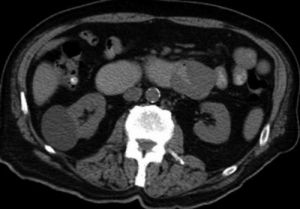

在器官浸潤上,髓外浸潤的位置以顱骨、眼眶等部位多見,也可見於乳腺、肝、腎或肌肉等處,髓系肉瘤也可發生於淋巴結內外。